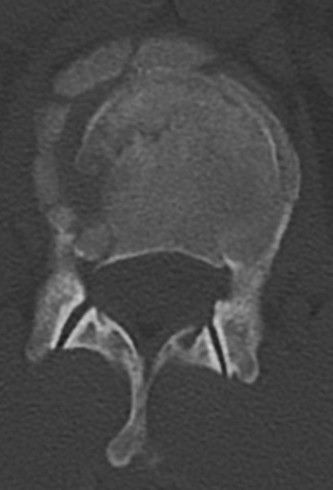

CASE 1 A 63-year-old male sustained a hyperextension injury to his neck while diving into a pool. Upon presentation, he reports decreased sensation in his hands and decreased strength in his arms and wrists, but no lower extremity complaints. On motor examination, he has 5/5 strength in his deltoids and elbow flexors and 4/5 strength in the elbow extensors, wrist extensors, and finger flexors. Lower extremity motor examination is normal. Sensation is decreased to light touch in both hands. Otherwise his sensation is preserved. Images of his cervical spine are shown in Figures 1–1 to 1–3.

Figure 1–1

The correct answer is (B). The clinical scenario describes a patient with central cord syndrome (CCS). CCS continues to be the most common incomplete spinal cord injury accounting for 15.7% to 25% of all spinal cord injuries. The characteristic presentation is an extension moment injury in a previously spondylotic and stenotic spine. Figures 1–1 to 1–3 demonstrate a spondylotic spine with central narrowing and CSF effacement that is worst at the C3–4 level. Bleeding, edema, and/or Wallerian degeneration lead to damage of the lateral corticospinal tract which is the main descending motor tract in the spinal cord. The more central anatomic position of the homunculus to the upper extremities places them at greater risk than those to the lower extremities. As such, injury to the lateral corticospinal tract is characterized by upper more than lower extremity involvement and motor deficits being more pronounced than sensory deficits.